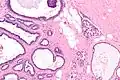

Collagenous spherulosis is characterized by a tubular/cribriform architecture with intratubular eosinophilic material that classically is arranged like the spokes of a wheel ("radial spikes"). There is usually no mitotic activity, and two cells populations (epithelial & myoepithelial) are present, like in benign breast glands.

The lesions are typically small (less than 50 spherules per lesion, less than 100 micrometers in size) and may be multifocal.